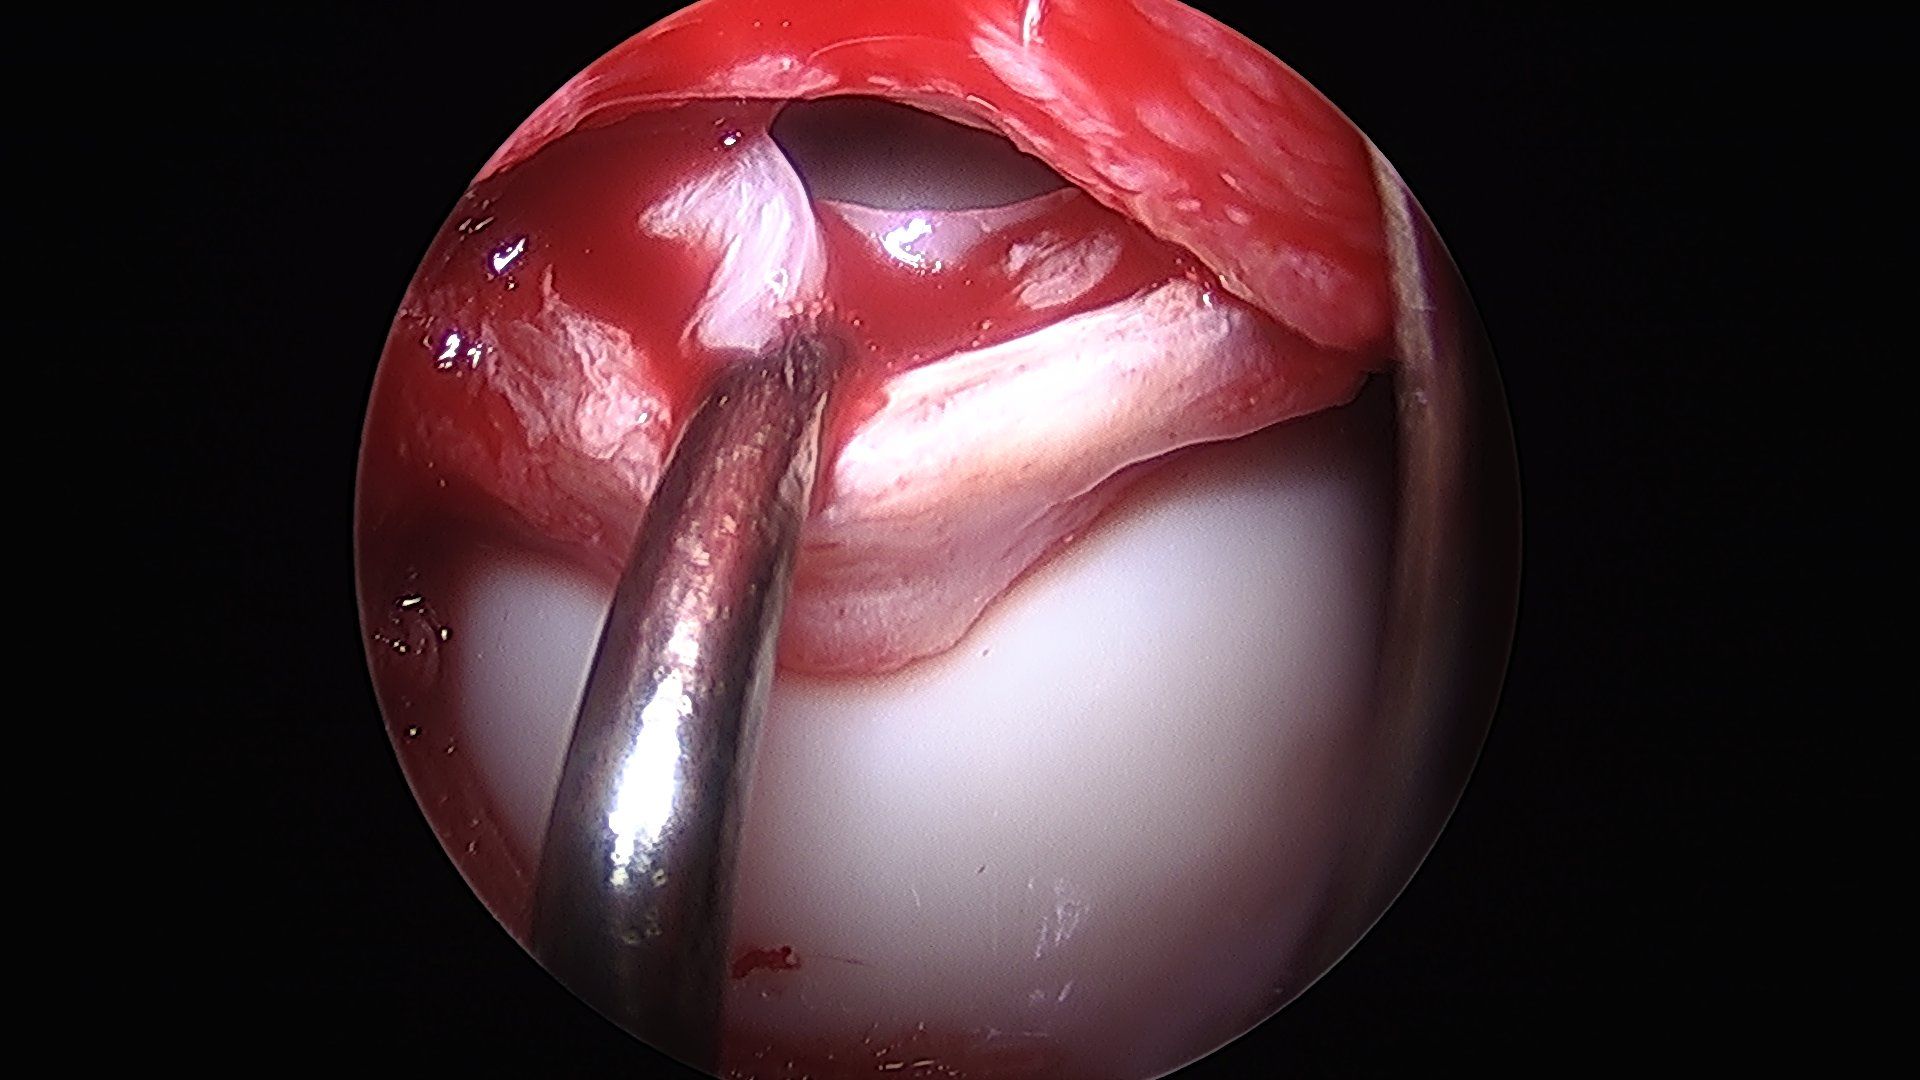

Details of the following steps have been described by (Hartmann and Gunther 2009). By disconnecting the traction device, a dynamic evaluation of hip motion under direct observation of labrum, head and neck is performed and the area of reshaping of the head–neck junction can be clearly defined (fig. 3d).

Visualisation of the central compartment of the joint for chondral and labral lesions is performed arthroscopically. After having applied distraction of the leg a 3.5 mm arthroscope (70° optics) is inserted from the anterior incision. Fluid management as in normal arthroscopy with continuous flow allows proper visualisation. The anterosuperior and lateral parts of the acetabular labrum with the adjacent articular cartilage and the femoral head are inspected. These are the areas where most of the relevant labrum and cartilage lesions are located. Depending on the amount as well as type of damage, reconstructive procedures are performed with and without traction. Ossified or ruptured parts of the labrum are resected or refixation of a partially detached labrum is performed with resorbable suture anchors (fig. 4a and 4b). Refixation of debonded cartilage flaps (fig. 5 a–d) curettage and microfracturing of damaged cartilage fragments and even autologous chondrocyte transplantation is possible (Bretschneider et al. 2020).

Contouring of the femoral head and neck by osteochondroplasty is performed with a partially covered acromionizer (fig. 6a and 6b).